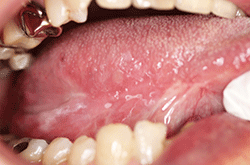

図❶ 初診時の右舌縁の所見

現病歴:いつからかは不明であるが、歯や床義歯が右舌縁と接触して痛みを自覚したため、近歯科医院にて調整を行っていたが改善なく、当科を受診(図❶)。細胞診を施行し、ClassIIIの結果で生検を行った。その結果、扁平上皮がん(以下、SCC)の報告があり、2006年5月、右舌がん切除術を施行した。その後、外来にて定期的な経過観察を行った。2017年11月、右舌縁に白色病変を伴った潰瘍を認め(図❷)、生検にてSCCの報告があり、再度舌部分切除術を施行した。以後、経過良好のため外来にて経過観察を行うも、2018年2月、腫瘍切除部位に有茎性の腫瘤を認めた(図❸)。